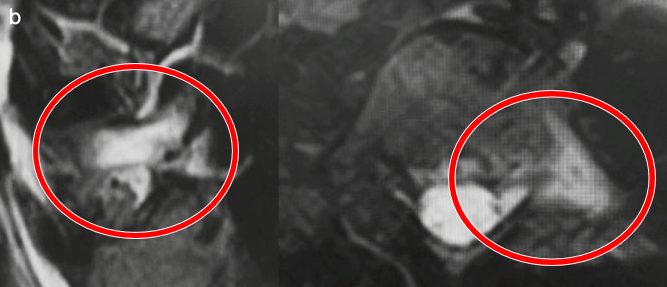

診断

診断は画像検査で行います。レントゲンでは関節間部というところに、隙間がないかを確認します。隙間や骨折線があれば分離症の診断となります。しかしながら、超初期はレントゲンでわからないため、疑ったらMRIを撮影します。MRIでは骨折部が骨浮腫を起こし、STIRという画像で高信号変化を示すことで診断ができます。